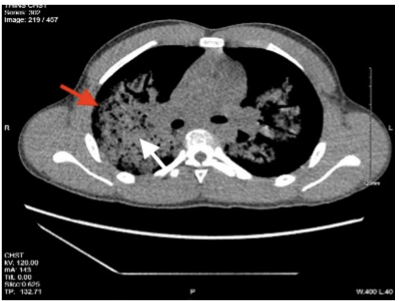

图:胸部CT扫描轴位图像显示多灶性肺泡腔模糊影(白色箭头)伴周围磨玻璃样影(红色箭头)

图:胸部CT血管造影(CTA)轴位图像,显示右肺动脉、左肺动脉及主肺动脉的典型充盈(红色箭头所示)

结合患者抗生素治疗无效、持续咯血及影像学表现,临床高度怀疑DAH,遂将其转入儿科重症监护室,给予吸氧(FiO₂ 30%)、容量复苏及万古霉素联合哌拉西林/他唑巴坦抗感染治疗。胸部CT显示双肺多灶性气腔实变及外周磨玻璃影,提示肺泡炎或肺出血;CT血管造影(CTA)排除肺栓塞。鉴于患者无白细胞增多、有明显嗜酸性粒细胞升高且对抗生素反应差,排除感染性病因后,于住院第2天开始经验性静脉输注甲泼尼龙(200mg/日),同时完善免疫相关检查。